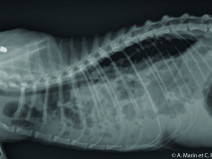

• Après-midi Travaux pratiques de radiographie / TP2 Le Thorax

Le GEIM vous propose une séance de travaux pratiques de radiographies sur le thorax. Tous les aspects sont abordés sous la forme de TP de lecture de radiographies numériques sur station de travail sur tablettes (deux vétérinaires maximum par tablettes).

• Travaux pratiques de radiographie / Le Thorax

Le GEIM vous propose une séance de travaux pratiques de radiographies sur le thorax. Tous les aspects sont abordés sous la forme de TP de lecture de radiographies numériques sur station de travail Osirix sur Mac (3 vétérinaires maximum/ordinateur).